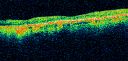

Diabetic Macular Ischemia - Enlarged FAZ - OCT-A447 views70 year old female diagnosed with diabetes 2 years ago. Her blood pressure was normal at 116/73. She has vision loss for 6 months in both eyes. VA is 20/100 OU. OCT-A shows macular ischemia.

Diabetic Macular Ischemia - Enlarged FAZ - OCT-A432 views70 year old female diagnosed with diabetes 2 years ago. Her blood pressure was normal at 116/73. She has vision loss for 6 months in both eyes. VA is 20/100 OU. OCT-A shows macular ischemia.

Diabetic Macular Ischemia - Enlarged FAZ - OCT-A426 views70 year old female diagnosed with diabetes 2 years ago. Her blood pressure was normal at 116/73. She has vision loss for 6 months in both eyes. VA is 20/100 OU. OCT-A shows macular ischemia.

Diabetic Macular Ischemia - Enlarged FAZ - OCT-A395 views70 year old female diagnosed with diabetes 2 years ago. Her blood pressure was normal at 116/73. She has vision loss for 6 months in both eyes. VA is 20/100 OU. OCT-A shows macular ischemia.